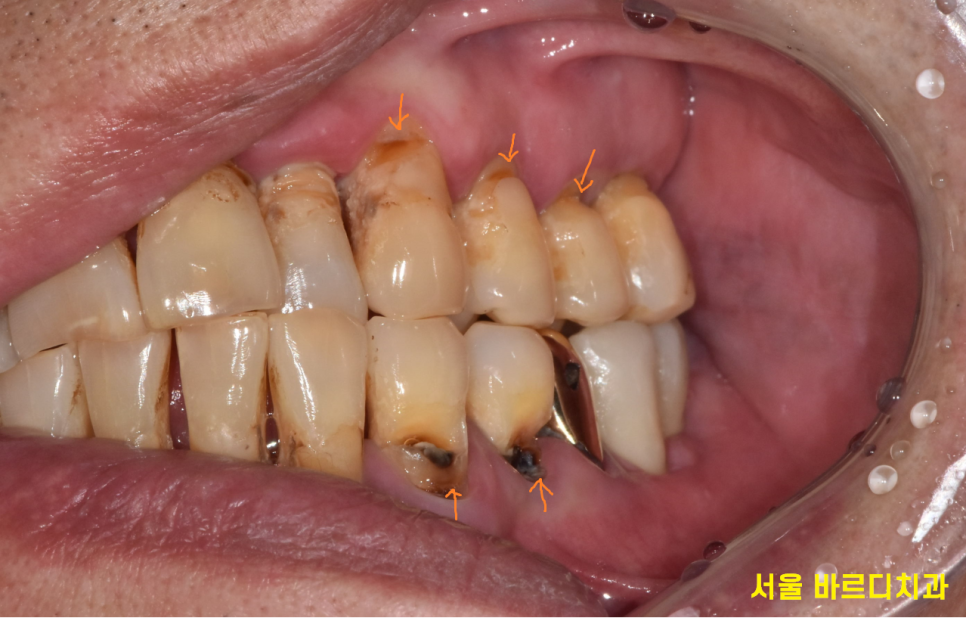

기타 증상으로는 녹아버린 잇몸뼈로

잇몸이 위로 올라가다보니 치아 뿌리 부분이 노출

양치가 안되면서 뿌리부분이 썩고,

전반적으로 파여있는 모습이었습니다.

ct도 찍어보고..

치아 상태가 전반적으로 흔들리고 안좋기 때문에

흔들리는 치아 중에서 몇개나 살릴 수 있을지

정밀 검사를 진행하였습니다.